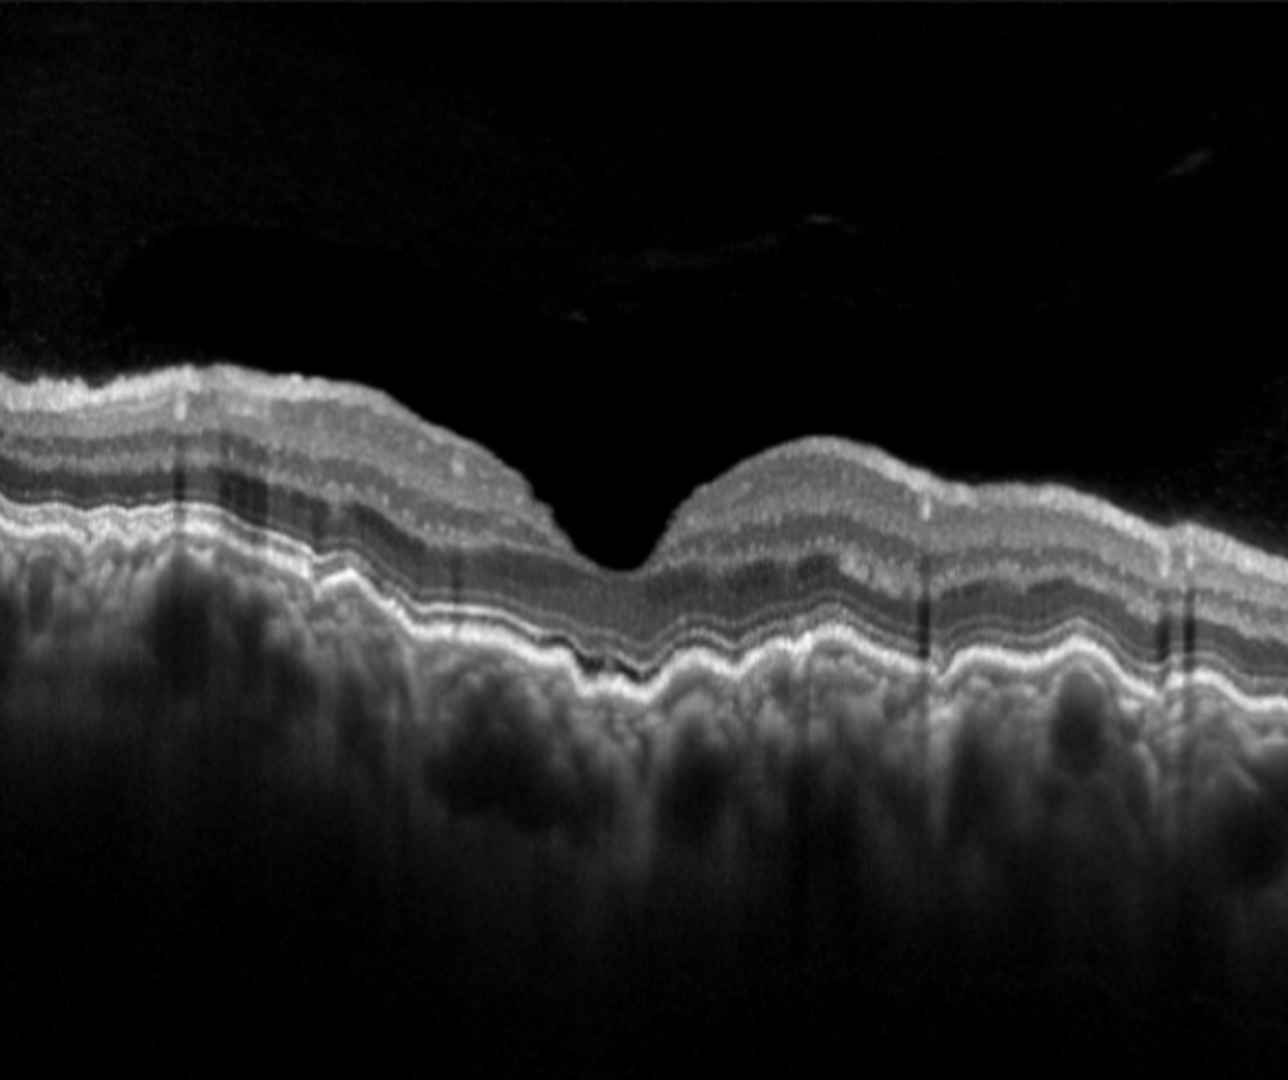

Choroidal folds are undulations of the outer retina (Bruch’s membrane, RPE and neurosensory retina) and the choroid. They are best appreciated on a vertical OCT line scan and may be distinguished from retinal folds caused by an epiretinal membrane using OCT.

Chorioretinal folds appear on retinal examination as a series of lines (typically alternating between yellow and dark).